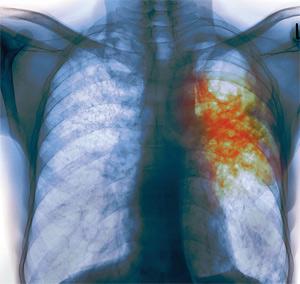

Оккупированными территориями Луганщины ширится эпидемия туберкулеза. Эпидемическая ситуация сложная и напряженная. Врачи опасаются, что неизлечимый туберкулез будет нещадно «косить» луганчан. Об этом на заседании коллегии «Министерства здравоохранения республики» заявила глава ведомства Лариса Айрапетян.

Наибольшую тревогу специалистов вызывает значительное количество деструктивных форм туберкулеза среди впервые выявленных больных, массивное бактериовыделение, увеличение распространенности химиорезистентного (устойчивого к препаратам) туберкулеза. Все это приводит к снижению качества лечения и, как следствие, – увеличению показателя смертности.

«Выводы неутешительны. Эпидемическая ситуация по туберкулезу – сложная и напряженная. Все население "республики" относится к группе риска. Если сейчас, пассивно сложа руки, мы ничего не сделаем в борьбе с химиорезистентным туберкулезом, то откроется второй невидимый фронт, и неизлечимый туберкулез будет нещадно «косить» население республики», - отметила Галина Роенко.